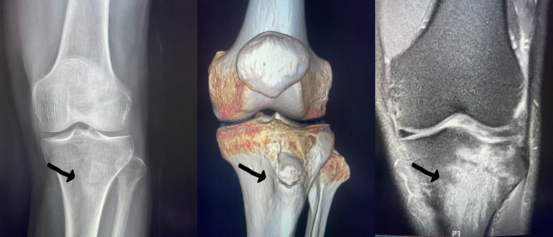

引言:一个真实故事 65岁的张阿姨最近总感膝盖疼痛,起初以为是关节炎,但服药一周未见好转。到医院后,医生建议她做磁共振(MRI)检查。结果发现,她的半月板撕裂严重,需立即手术!"以前觉得MRI贵且麻烦,没想到它竟能精准揪出'隐藏'的病灶!"张阿姨感慨道。 其实,像张阿姨这样的情况并非个例。近年来,MRI凭借其"软组织侦探"的本领,已成为骨关节疾病诊断的"金标准"。本文带你揭秘MRI在骨关节领域的独特优势,助医生精准决策,患者明明白白就医! MRI如何"看"骨关节?——原理篇 通俗版解释:MRI通过强大的磁场和无线电波,让人体内的氢原子(就像无数小磁针)排列整齐,再通过计算机重建出骨骼、肌肉、韧带的高清图像。相比X光和CT,MRI能更清晰地显示"软组织"(如软骨、肌腱),就像给关节拍一张"立体解剖图"。 MRI的"超能力":骨关节疾病的精准打击 1. 关节炎早期预警 MRI可发现关节滑膜增生、软骨磨损等细微病变,比X光早3-6个月确诊类风湿性关节炎。 2. 韧带损伤"一目了然" 扭伤膝盖后,MRI能清晰显示前交叉韧带是否断裂、水肿程度,为手术方案提供依据。 3. 隐匿性骨折不漏诊 老年人轻微摔倒后,X光未见明显骨折线,MRI却能发现骨髓水肿,提示"隐性骨折",避免延误治疗。 4. 肿瘤筛查更安心 MRI对骨肿瘤的良恶性鉴别准确率达90%以上,且无需注射造影剂即可观察肿瘤边界。 为什么医生更爱选MRI?——六大核心优势 X线片 CT三维重建 MRI扫描 似见骨折线影 骨折线清晰可见 大片状骨髓水肿 合并半月板损伤 (此图为同一患者三种检查方法直观区别及相互补充) 患者必读:MRI检查的那些事儿 Q1:MRI检查贵吗?多久能出结果? A:根据扫描部位和扫描方式的不同价格有所不同,但多数医保可报销。常规检查约10-30分钟,报告通常24小时内出具。 Q2:检查时需要脱衣服吗?有金属物品禁忌吗? A:需换上无金属衣物或使用专用检查服。体内有心脏起搏器、金属假牙者需提前告知医生。 Q3:孕妇和儿童能做MRI吗? A:孕妇建议孕3个月后检查,儿童需由家长陪同并在医生指导下进行。 合理应用MRI:既要"精准",也要"适度" 虽然MRI优势显著,但并非所有骨关节问题都需做MRI。例如:急性外伤骨折首选X光,钙化性病变CT更敏感。建议患者在医生指导下,结合症状和体征选择最适合的检查方案。 结语:让科技为健康护航 "避免盲目追求'最贵'检查,而是要让每项检查都发挥最大价值——这才是精准医疗的核心!" MRI不仅是诊断工具,更是守护骨关节健康的"智慧之眼"。当临床医生与患者携手,科学选择检查手段时,我们离"早发现、早诊断、早治疗"的目标又近了一步 |